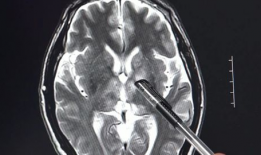

脑膜刺激征检查视频,直观解析临床诊断技巧

你有没有想过,去医院看病的时候,医生有时候会给你来点“特殊待遇”?比如说,给你做个脑膜刺激征检查。这听起来是不是有点陌生?别急,...